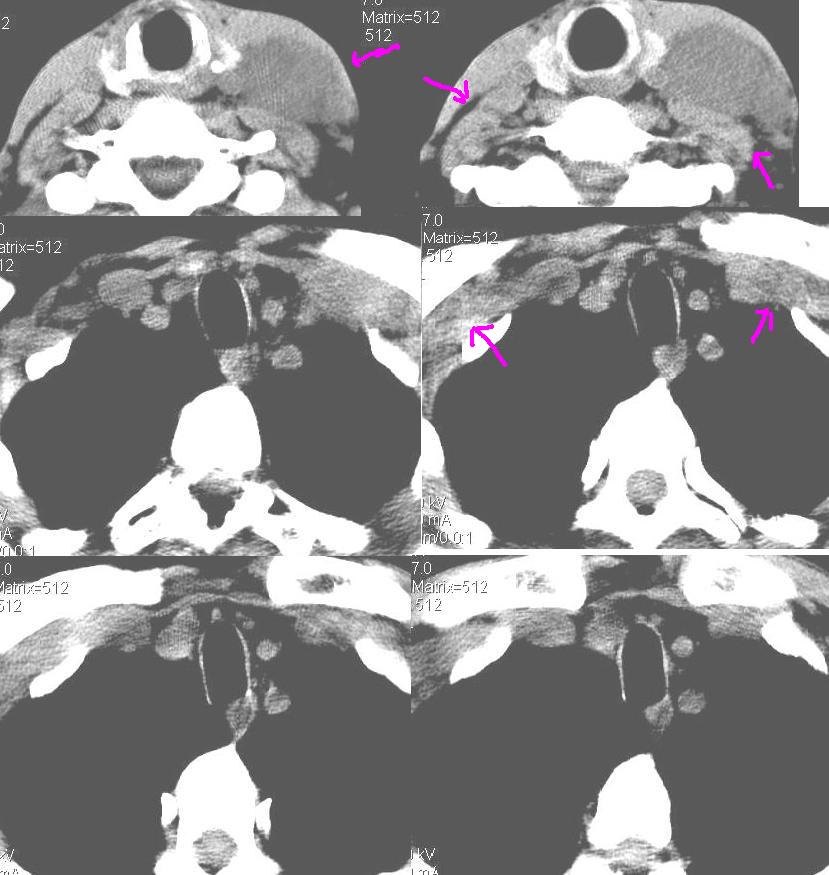

上腹部疼痛一月,呕吐10天,发现左侧颈部包快10天 胸部cr片未见明显异常。

左侧胸锁乳突肌下方、颈血管旁低密度肿块影,肿块密度尚均匀,边缘大部分清楚,邻近组织稍受压移位。考虑颈部神经鞘瘤可能性大。

黑!广泛淋巴结肿大不符合胰腺癌转移。胰腺周围淋巴结肿大致使胰腺看起来大。考虑淋巴瘤可能大。

颈部及腹膜后淋巴瘤可能性大